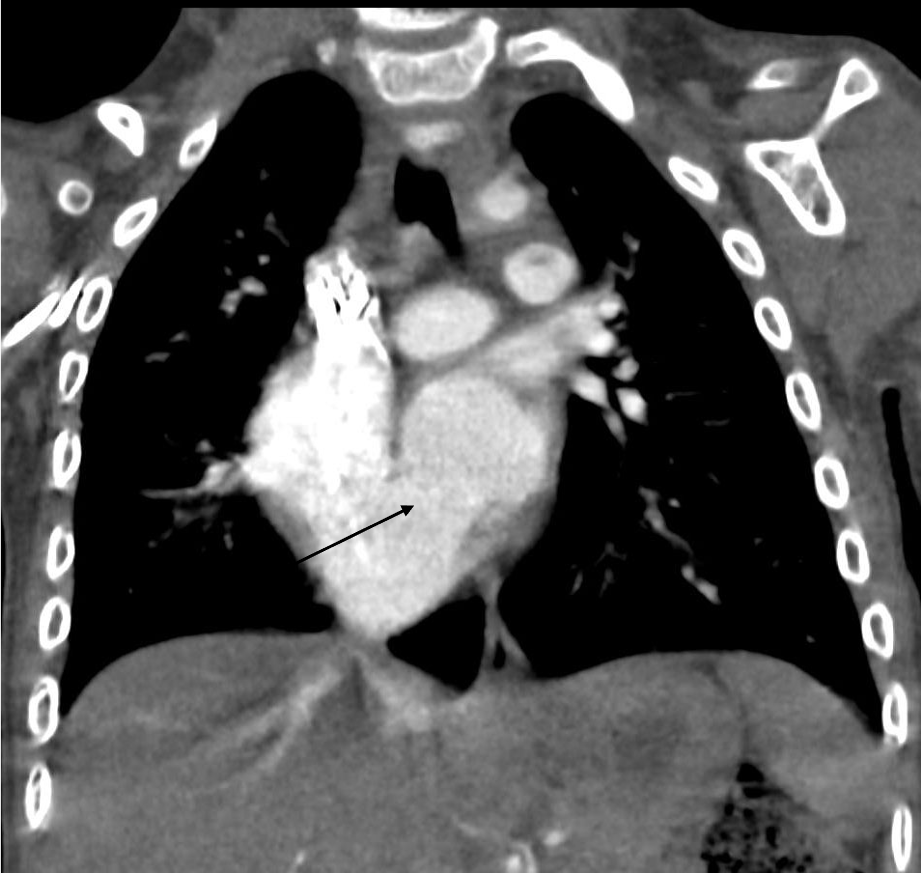

3歳、 男児、 9kg、 心房中隔欠損

染色体異常が判明している男児。肺炎で入院した際のレントゲンで右心系の拡大を指摘された。心臓超音波検査にて心房間の短絡が疑われた。心房中隔欠損症疑いの精査、肺静脈還流異常の除外目的で造影CT検査が施行された。

心房中隔欠損症は左右の心房に短絡を生じる先天性の病態である。欠損部位により、二次孔欠損、一次孔欠損および冠静脈洞欠損に大別される。まず身体所見、胸部レントゲン写真および心電図検査が行われ、解剖学的構造を評価するために、心エコー検査が施行される。心エコー検査で十分な情報が得られない場合、欠損孔の部位や形態を評価するために造影CTが施行される。最終的な治療方針の決定にはカテーテル検査が施行されることが多いが、あらかじめ病変の形態や解剖を把握するために造影CTは有用である。また肺静脈還流異常を合併することがあるため、その有無を評価することができる。短絡が小さいものについては経過観察が可能であるが、ある程度大きい病変に対しては治療が必要となる。治療はカテーテルによる閉鎖術、外科手術が挙げられる。カテーテルによる閉鎖術が選択される場合には、造影CTは治療計画用にも用いられる。その場合には、任意多断面再構成(MPR)やvolume rendering(VR)像などを活用する。